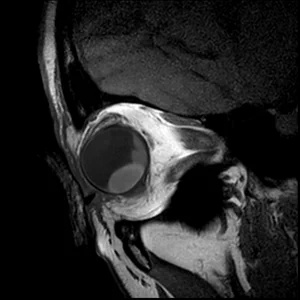

• 2D T2

2D T2

The high in-plane resolution allows for accurate assessment of the lesions origin and relation.